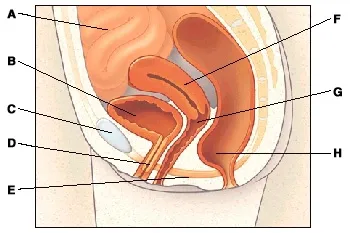

What is a normal pelvis?

A. The small intestine absorbs nutrients from food.

B. The bladder collects and holds urine.

C. The pubic bone helps protect the pelvic organs.

D. The urethra is the tube that carries urine out of the body.

E. The pelvic floor muscles support organs and other structures in the pelvis.

F. The uterus is where the baby develops when a women is pregnant.

G. The vagina is the canal from the uterus to the outside of the body.

H. The rectum stores stool until a bowel movement occurs.